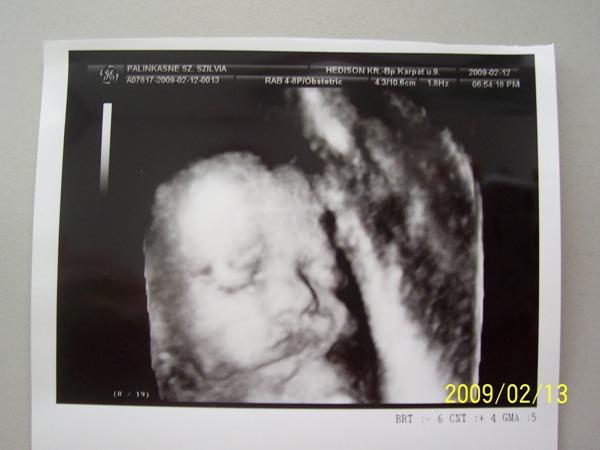

Kicsit bánt hogy nem sok minden látszott meg nincs adat Hannáról így ha apuka itthon lesz elmegyünk 4 D-re.

4D-re két hét múlva megyünk. Már nagyon kíváncsi vagyok.

Na voltunk tegnap 4d-n. Minden rendben van. Még mindig kislány!

BPD: 6,73

HC: 26,4

AC: 21,8

FL: 5,24

1030 gramm

Szóval minden rendben és nagyon aktív volt :D

Más. Tegnap voltunk 4D-n! Nagyon jó volt látni Áron pofiját. Tiszta apja, akárcsak Alíz. Viszont a dokinő szerint is óriásbébi lesz, azt mondta ennyi idős babán ennyi husit, ilyen combokat még nem látott, pedig a szakmában van egy ideje. 28 hetes (ez biztos), de Ő 30-nak mérte! már 1560 g! Kezd elszállni a reményem, hogy másodszorra megúszom a császárt!